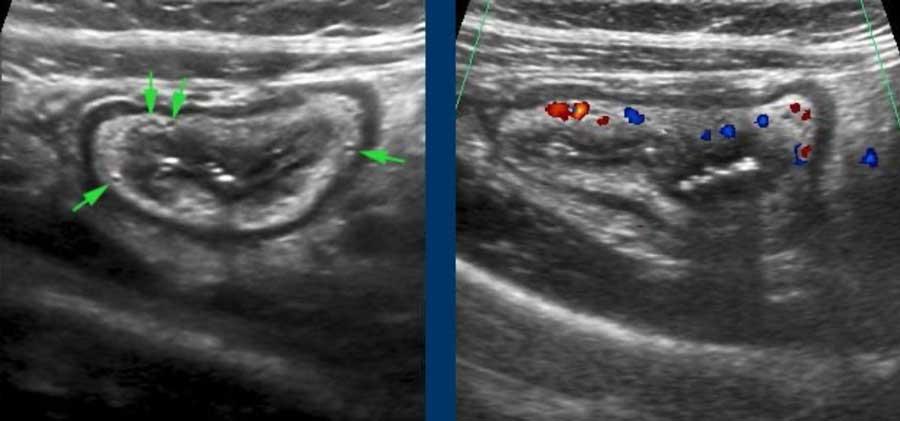

Lớp dưới niêm mạc chứa các mạch máu, dây thần kinh và mô mỡ, có tính chất tăng âm do chứa nhiều mô liên kết lỏng lẻo.

Ở bệnh nhân viêm loét đại tràng này, các mạch máu nổi bật (mũi tên) trong lớp dưới niêm mạc được hiển thị và xác nhận bằng Doppler màu ở hình bên phải.

Lớp dưới niêm mạc “kết nối lỏng lẻo” niêm mạc với lớp cơ, và trong quá trình co bóp, lớp dưới niêm mạc có thể được nhìn thấy đi theo các nếp gấp niêm mạc (trên bên trái).